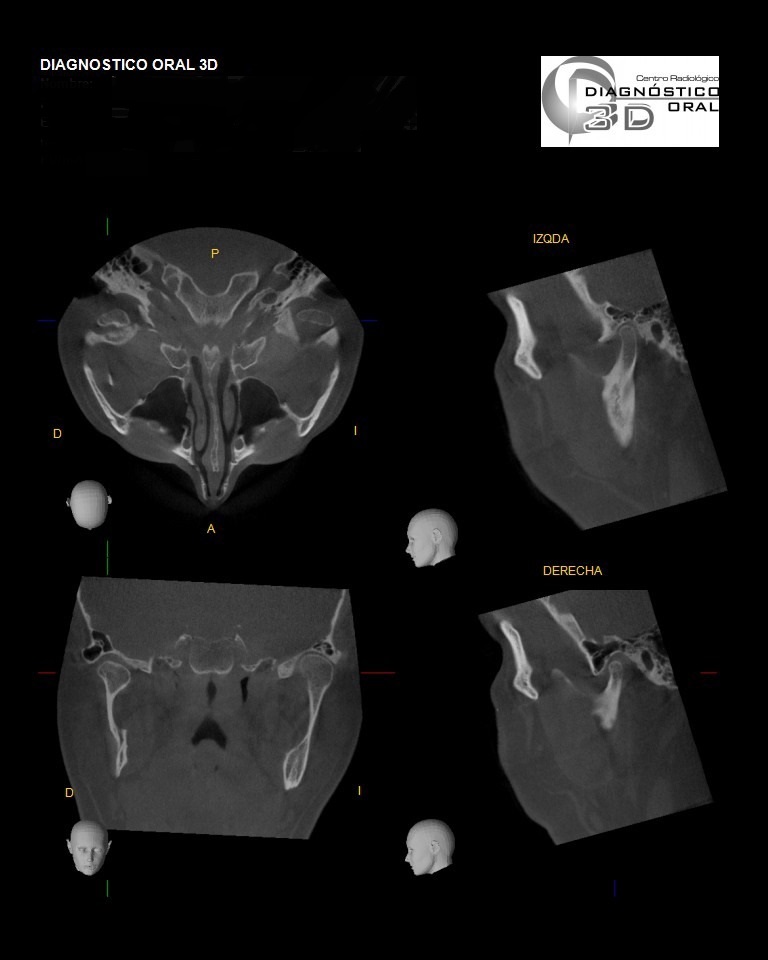

El Centro Radiológico Diagnóstico Oral 3D, es una empresa antioqueña que ofrece a sus pacientes desde el año 2009, tecnología de vanguardia en radiografías tridimensionales con calidad fotográfica. Las posibilidades para mejorar la eficacia en los diagnósticos bucales son evidentes, también lo son las posibilidades de manipulación de imagen. El sistema de imágenes en 3D ofrece detalles sin precedentes, convirtiéndola en la opción idónea para la mayoría de aplicaciones odontológicas, incluyendo implantes, tratamiento de conductos, ortodoncia, odontopediatría, periodoncia y cirugía

El mayor beneficiado con el uso de esta tecnología es el paciente, el cual podrá ser evaluado en todas sus dimensiones con una baja dosis de radiación, con un costo accesible y sin contaminar  el medio ambiente. Dependiendo de la necesidad del paciente, hay varios tipos de tomografías y los especialistas en el área odontológica hacen uso de ellas según su especialidad.

Evaluación de patologías dentales y maxilofaciales

Planificación de tratamientos ortodónticos y ortognáticos

Evaluación pre y postoperatoria de cirugías maxilofaciales